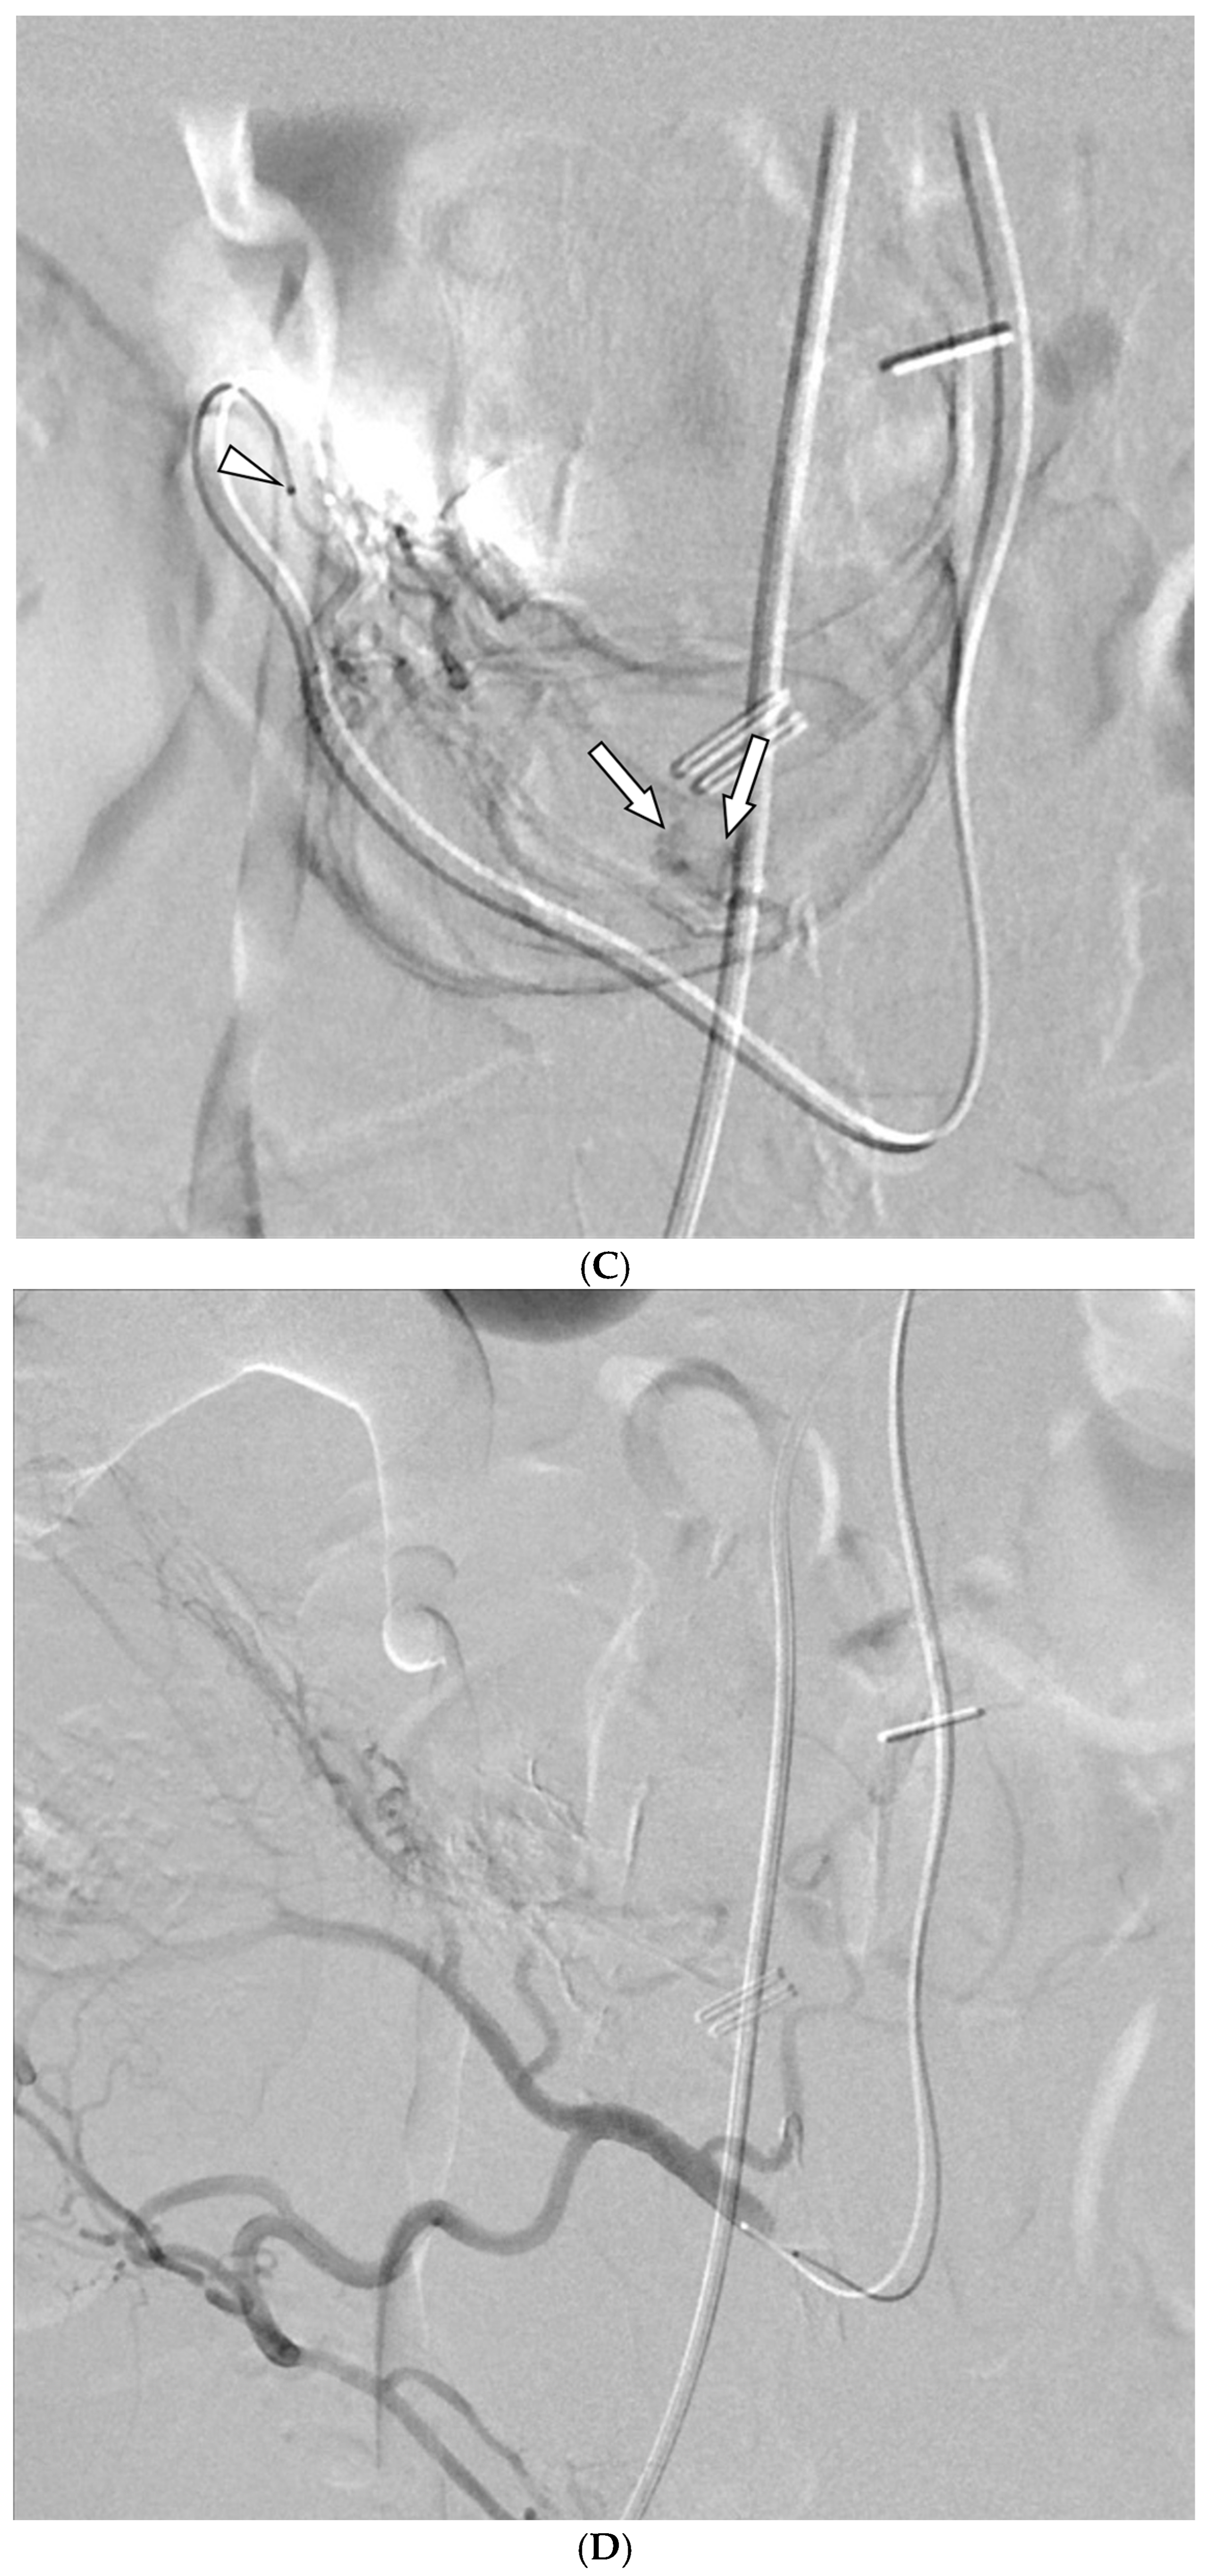

- Alali, M.; Cao, C.; Shin, J.H.; Jeon, G.; Zeng, C.H.; Park, J.-H.; Aljerdah, S.; Aljohani, S. Preliminary report on embolization with quick-soluble gelatin sponge particles for angiographically negative acute gastrointestinal bleeding. Sci. Rep. 2024, 14, 6438. [Google Scholar] [CrossRef]